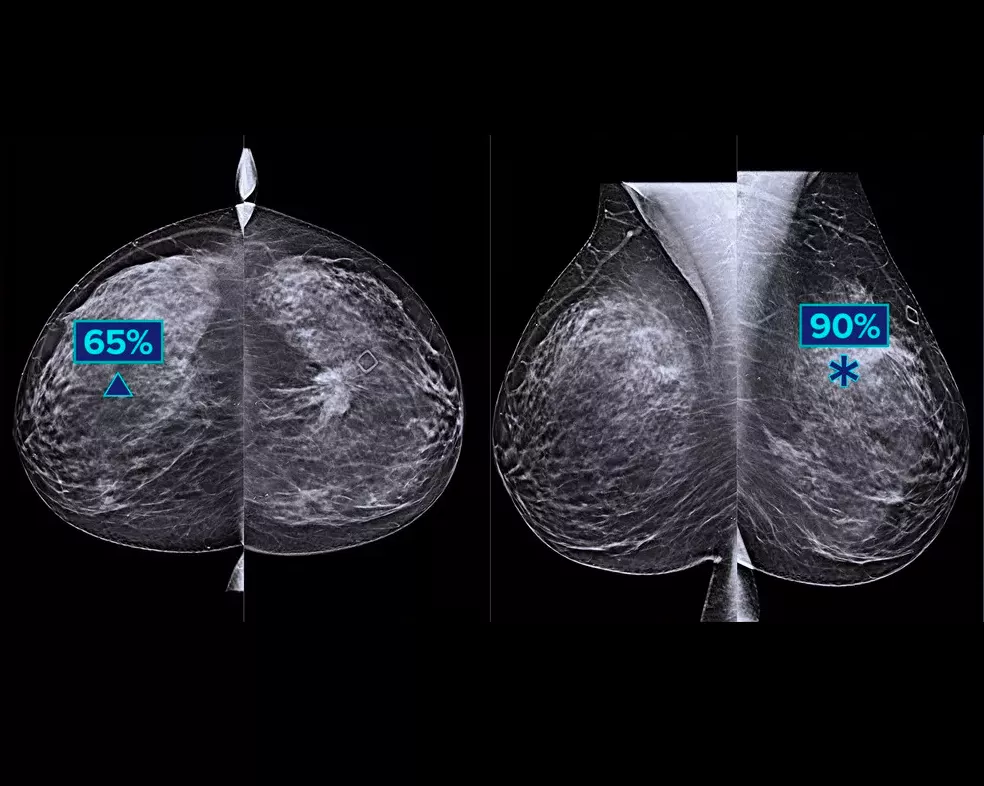

Un algoritmo de aprendizaje profundo diseñado para ayudar a los radiólogos en el diagnóstico y la detección del cáncer de mama1-3 en imágenes de tomosíntesis obtenidas con los sistemas Dimensions Mammography® de Hologic. El algoritmo localiza posibles lesiones compatibles con cáncer de mama, mediante la exploración de cada uno de los cortes del conjunto de imágenes de tomosíntesis. Las zonas sospechosas se resaltan para la lectura simultánea en la estación de trabajo del radiólogo y ayudar a la interpretación.

El algoritmo busca los tres grupos principales de lesiones sospechosas: calcificaciones, masas, densidades y distorsiones, y las combinaciones de estas lesiones. Los resultados pueden variar dependiendo de la estación de trabajo de lectura.